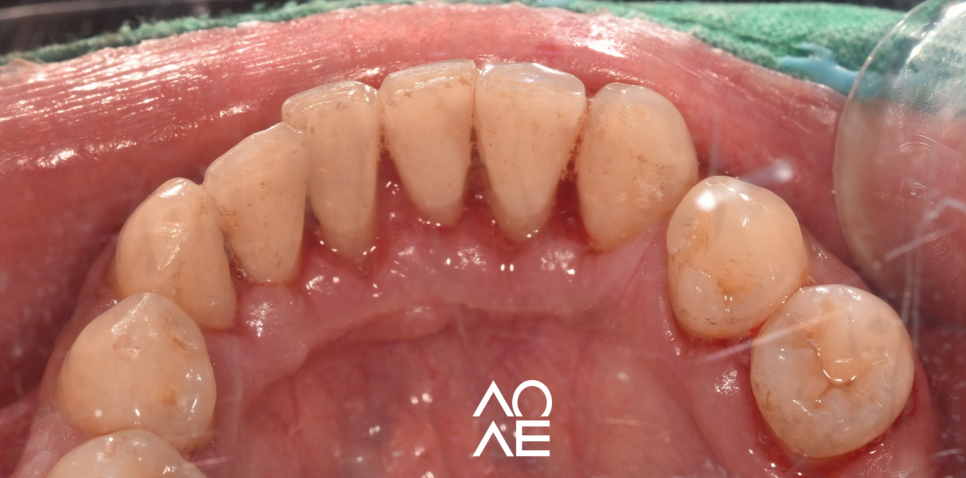

아래 사진은 인터넷에

떠돌아다니는 사진이 아니라

저희 치과에서 스케일링을 받으신

30대 후반의 남성이신데요.

몇 년에 걸쳐서 한 번도 치과에 오지 않으셨데요

촬영일 24. 3월 20일

초점이 좀 맞지 않긴 했지만,

실제 치석이 두껍게 붙어있는게

쉽게 구분이 되시죠?

단순히 치석만 붙어 있는 상태가 아닌,

잇몸도 치석으로 인해서 부어있고

치료가 필요한 상황이었습니다

어떠신가요?

그냥 보기에도 좋아보이시죠?

간단한 스케일링으로 이렇게

구강 건강을 개선할 수 있습니다.